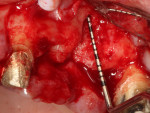

The surgery was performed using the standard aseptic surgical protocol. Full-thickness flap elevation from teeth Nos. 11 through 14 was necessary to expose position No. 12, enable extraction of tooth No. 13, and adequately debride the socket, with removal of any soft-tissue remnants (Figure 2). A large buccal dehiscence lesion was noted, which was a result of the fractured bicuspid (Figure 3).